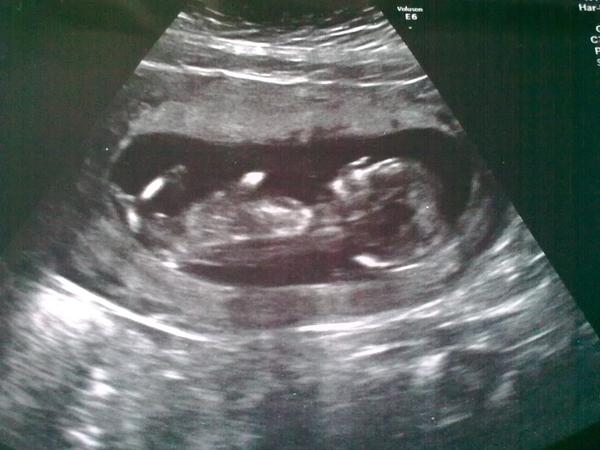

Ahoj holky, mám dotaz, včera jsme byli na screeningu, doktor koukal na mimčo, změřil šíjové projasnění,které bylo 2, ukazoval nohy, ruce, moč. měchýř, žaludek. jsme prý o týden starší než podle MS, takže jsme 13+5, nakonec vypočetl riziko a byl nadšený, že nám to krásně vyšlo, že nám gratuluje, že je vše v pořádku, když jsem si pak četla zprávu, všimla jsem si, že tam není napsané nic o nosní kůstce, tak se na to manžel šel ještě zeptat doktora a ten řekl, že to pro něj není podstatné, že nám to vyšlo vše krásně a je to v pořádku. tak co si o tom myslíte? když jsem čekala první dceru, tak jsem to ve zprávě napsané měli. jsem z toho nervózní ☹ jinak to riziko nám vyšlo 1: 13650.

Ahoj, to byl utz u tvého doktora nebo jsi byla speciálně na NT i s krví? Mně totoiž moje doktorka taky měřila šíjové prijasnění, kontrolovala orgány atd., ale na NT+ jsem byla na klinice na vlastní žádost za vlastní peníze. Tak mi brali krev a tu pak dávali dohromady s podrobným utz včetně projasnění a kůstky. Možná už se to ale dělá zase jinak.